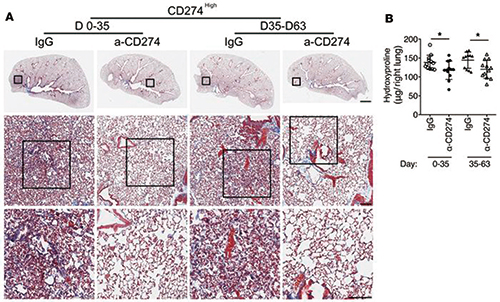

PD-L1抑制剂或可治疗特发性肺纤维化?

PD-L1抑制剂或可治疗特发性肺纤维化?

2019-04-02 11:30:52

一项研究显示,与癌症生长相关的蛋白质或能治疗致命性的肺部疾病——特发性肺纤维化。该结论得自小鼠模型和人体组织样本,在PD-L1抑制剂抗肿瘤治疗时或可同时治疗该病。(JCI …